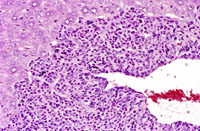

Myelodysplasia with primarily periportal myeloproliferation. Higher magnification shows bridging of cellular infiltrates between portal areas and hyaline degenerative changes in hepatocytes.